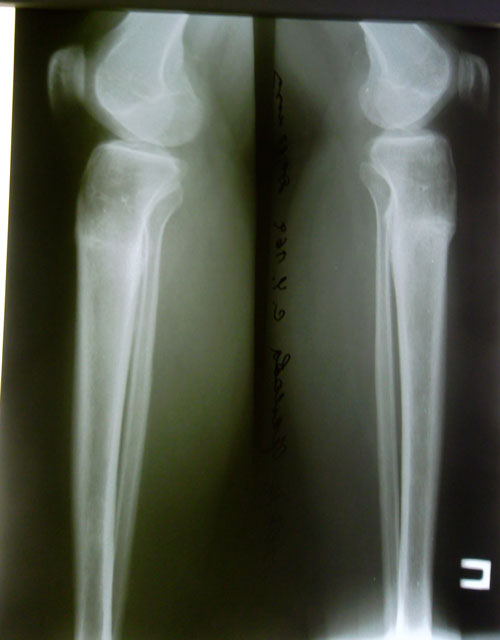

Диагноз: О-образная деформация ног

Дата операции 25.09.2013г.

Исходник.